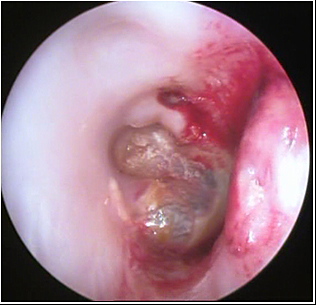

JFC Otitis media supurativa crónica. Colesteatoma.

JFC Otitis media crónica colesteatomatosa.